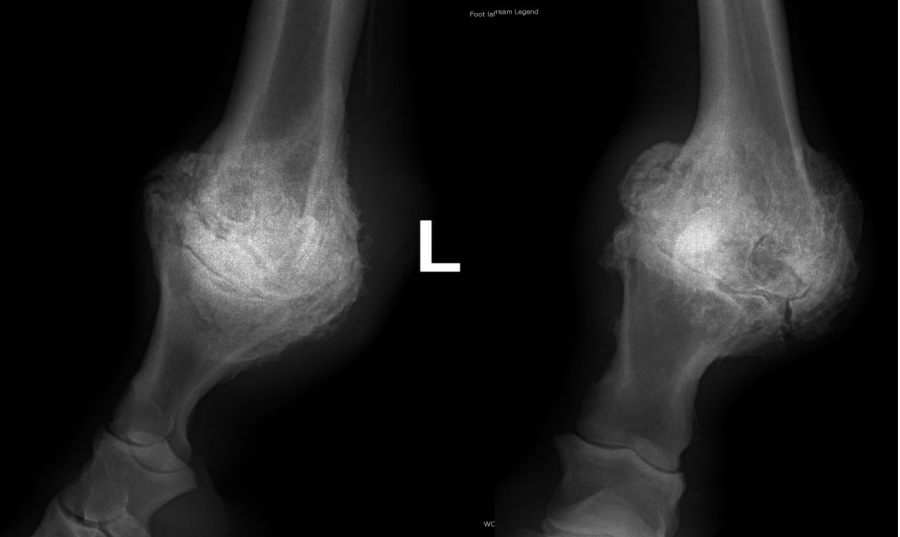

Ankylóza spěnkovýho kloubu

Těžká artróza ve spěnkovém kloubu